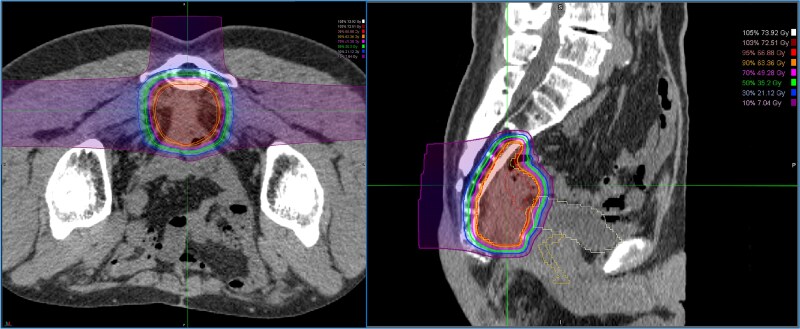

Treatment of locally recurrent rectal cancer (LRRC) after surgery is often complex and challenging. A 52-year-old man received emergency surgery (Hartmann's procedure) for bowel perforation caused by a huge sigmoid colon cancer, followed by treatment for concurrent advanced lower rectal cancer with neoadjuvant chemoradiotherapy and abdominoperineal resection. A solitary lung metastasis emerged afterwards, and was surgically removed. However, the patient developed LRRC in front of the sacrum. As surgical resection for the local recurrence was considered too invasive, carbon-ion radiotherapy (CIRT) was performed as radical local therapy. Because the surrounding intestine was highly adherent to the tumor and there was a high risk of developing an ulcer, the intestine was prophylactically resected. The patient has remained relapse-free for 2 years and 6 months since the most recent surgery. CIRT for LRRC appears to represent a useful therapeutic option in combination with prophylactic intestinal resection.